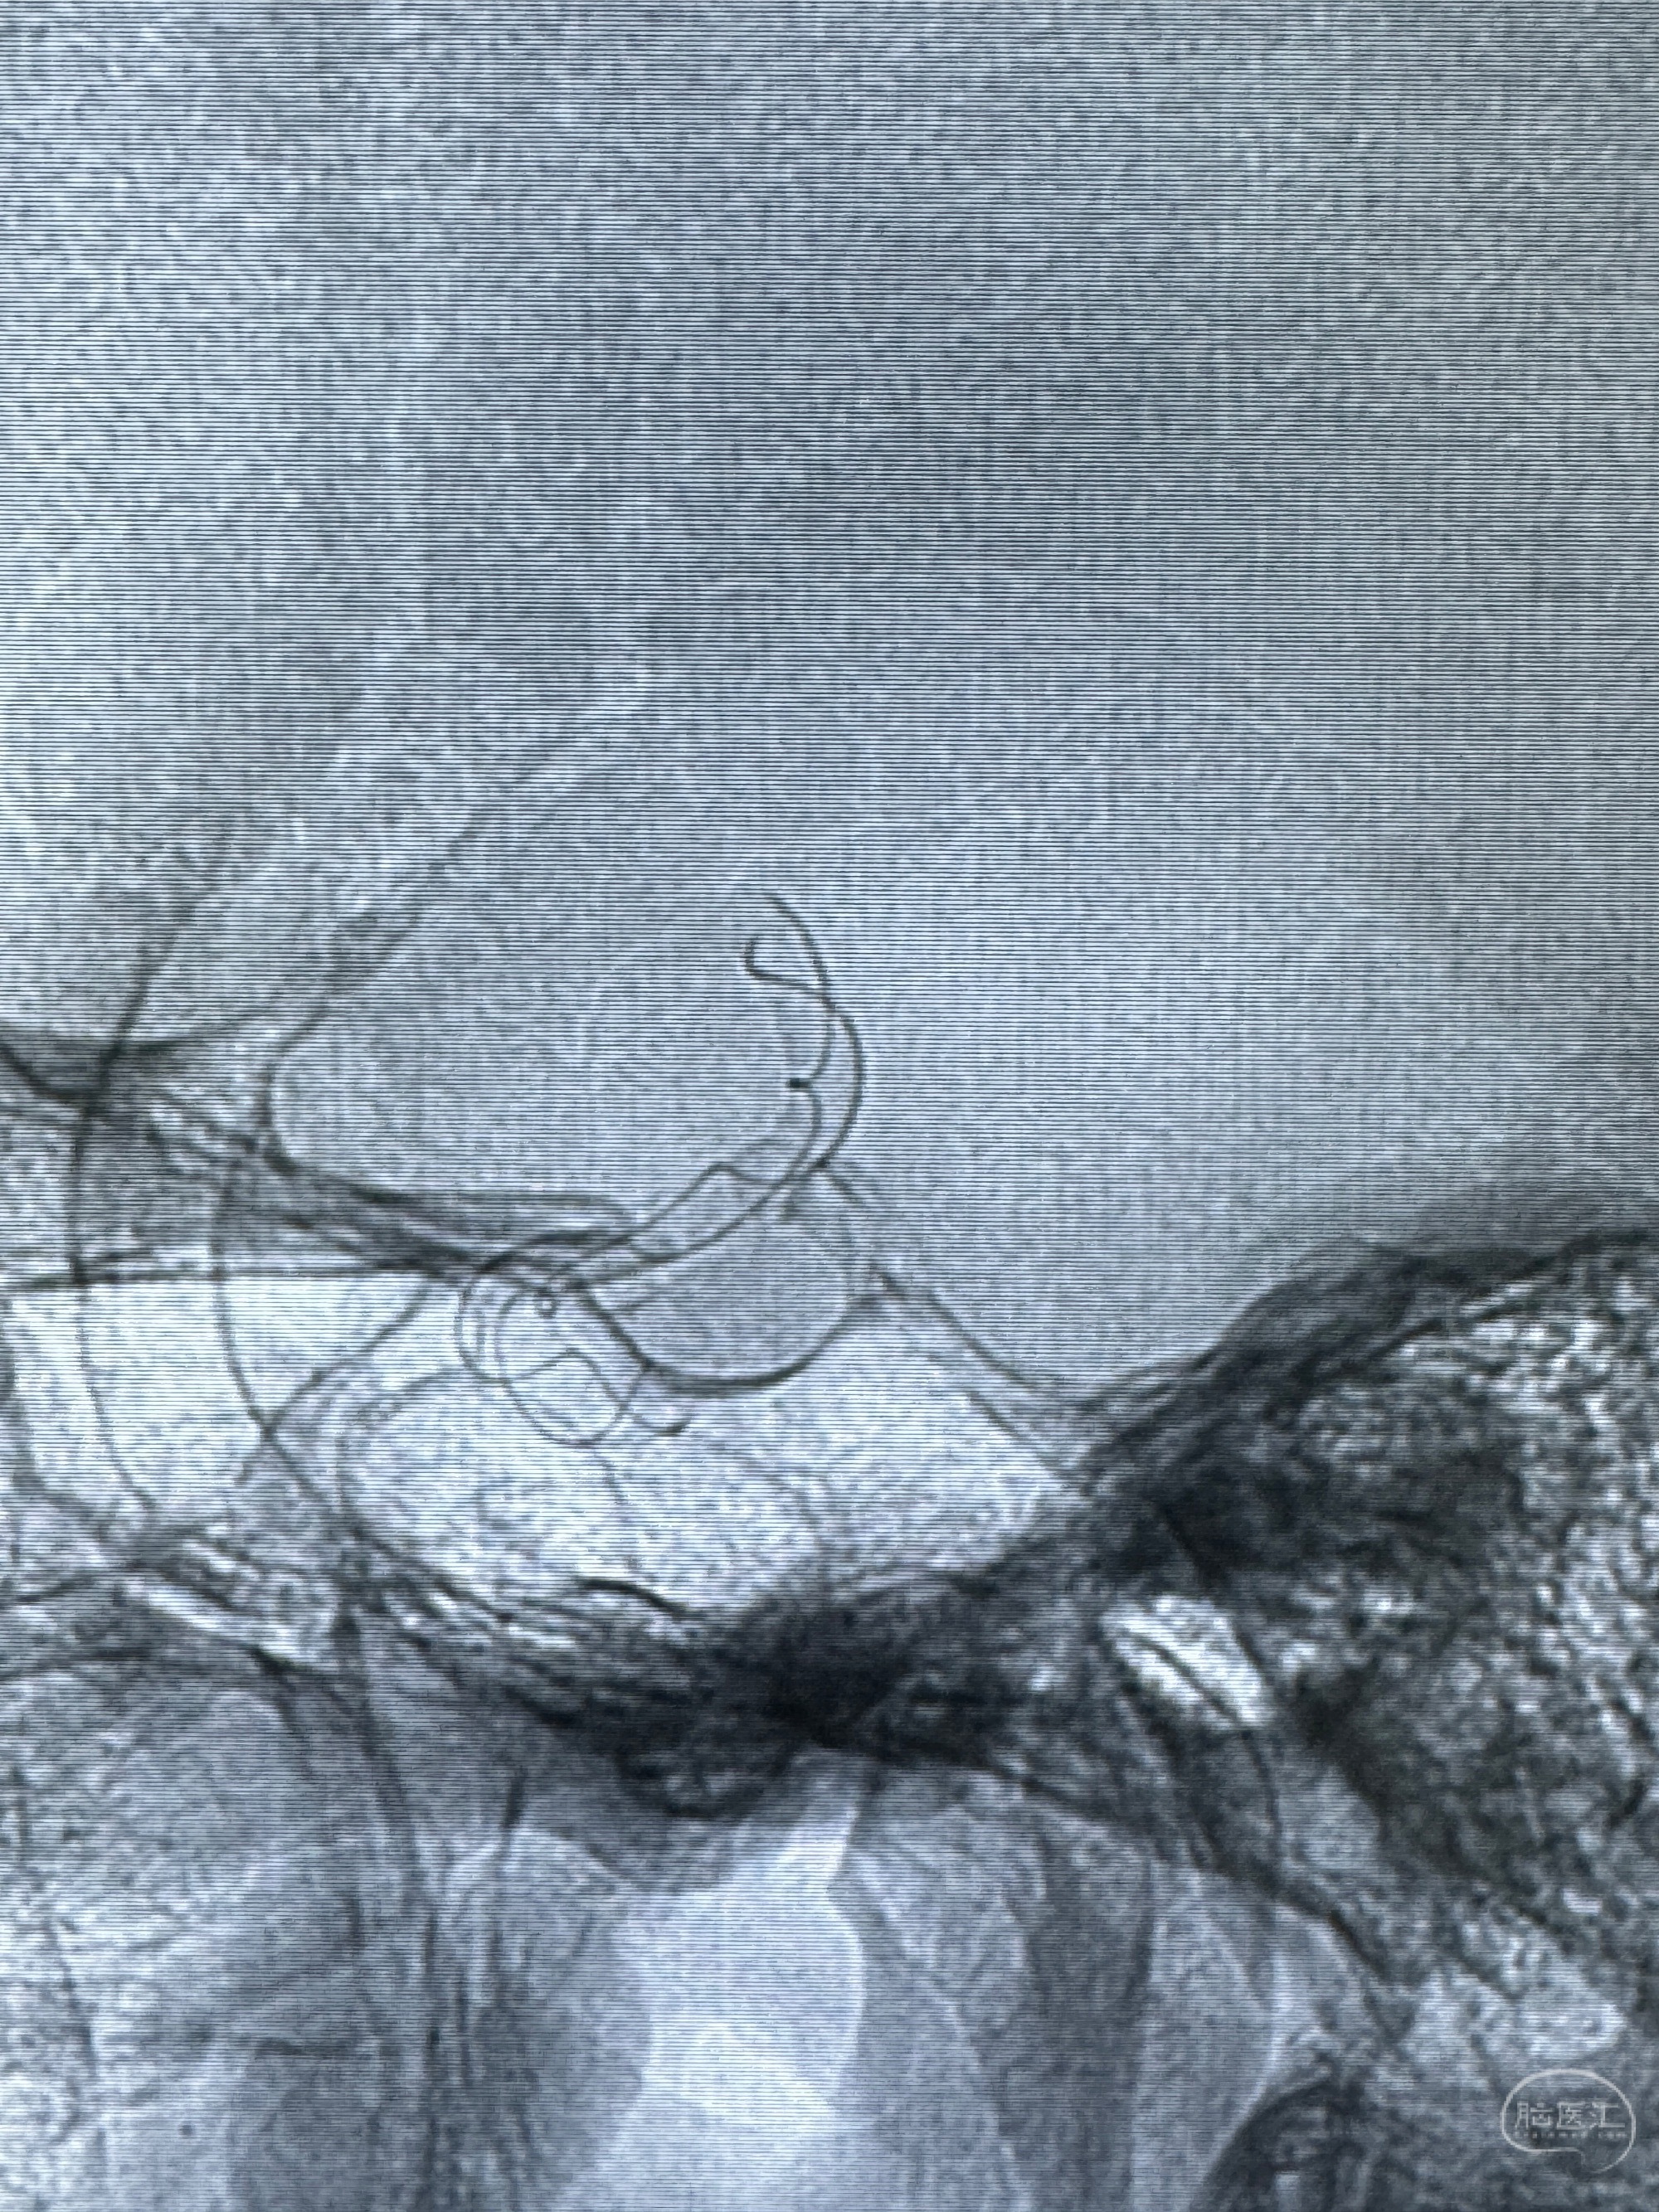

透视可见红圈部分为支架导管的头端

手推冒烟显示支架位置及展开情况,箭头为支架导管的位置

尝试回收支架失败,只能考虑释放支架了

逐帧图像展示歪着脖子释放支架,旁边吩咐助手手机摄影、拍照留像(透视机不能留影像)